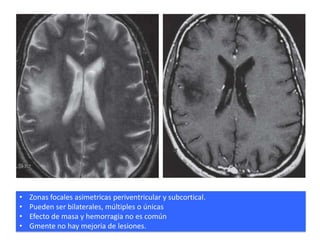

•   Zonas focales asimetricas periventricular y subcortical.

•   Pueden ser bilaterales, múltiples o únicas

•   Efecto de masa y hemorragia no es común

•   Gmente no hay mejoria de lesiones.

Zonas focales asimetricas periventricular y subcortical. • Pueden ser bilaterales, múltiples o únicas • Efecto de masa y hemorragia no es común • Gmente no hay mejoria de lesiones.